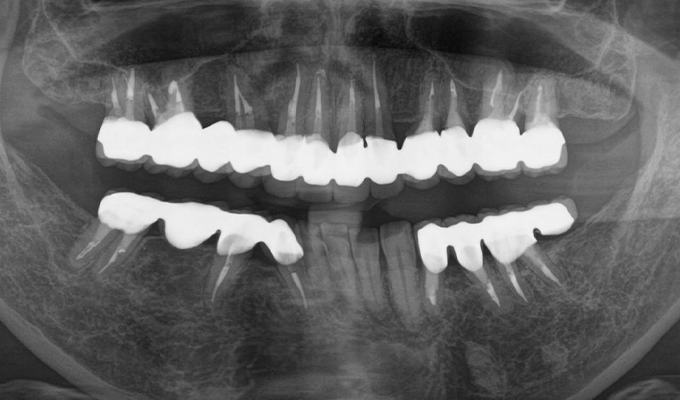

case1インプラントとメタルボンドブリッジの症例

初診時(2010年)

初回メンテナンス時(2014年)

最新メンテナンス時(2024年)

- 初診時の年齢

- 60代女性(2010年)

- 主訴

- ちゃんと咬めるようになりたい。最近孫が生まれたから一緒に歌ったりしたいけど、今は歌うこともできないから・・・・。と

- 治療内容

- 5年ほど前に入れ歯を作ったそうですが合わなかったので使用してなかったせいか前歯がグラグラになっていて今にも抜けそうな状態でした。

保存が難しい歯を抜歯し、上はインプラント8本、下は奥歯にインプラント4本埋入しました。

補綴は変色しないメタルボンドを選択されたので治療完了して11年経過してもとてもきれいな状態で維持されています。

初診時にお話しされていたお孫さんも中学2年生になったそうで、歯の治療をしたおかげで充実した毎日が送れてます、とメンテナンス時もいつも嬉しそうにされています。